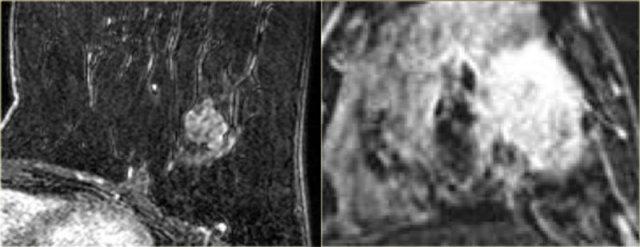

Ngấm thuốc đồng nhất

Hình ảnh bên trái cho thấy một tổn thương ngấm thuốc đồng nhất.

Tổn thương này được xác định là ung thư biểu mô ống xâm nhập.

Ngấm thuốc không đồng nhất

Bên trái, hình ảnh cho thấy một khối có hình dạng bất quy tắc với các tua gai và kiểu ngấm thuốc bên trong không đồng nhất, được xác định là ung thư biểu mô tiểu thùy xâm nhập.